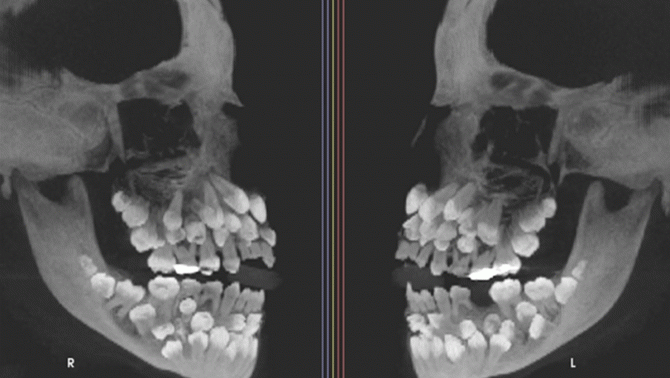

"bé gái có 81 chiếc răng" - Bác sĩ giật mình khi phát hiện bé gái 11 tuổi có đến 81 chiếc răng, thách thức quá trình điều trị

Bác sĩ giật mình khi phát hiện bé gái 11 tuổi có đến 81 chiếc răng, thách thức quá trình điều trị

Về mặt nha khoa, tình trạng có đến 81 chiếc răng của bé gái gây nhiều thách thức trong điều trị. Việc nhổ bỏ toàn bộ răng siêu thừa phải được tính toán kỹ lưỡng để tránh tổn thương đến xương hàm.